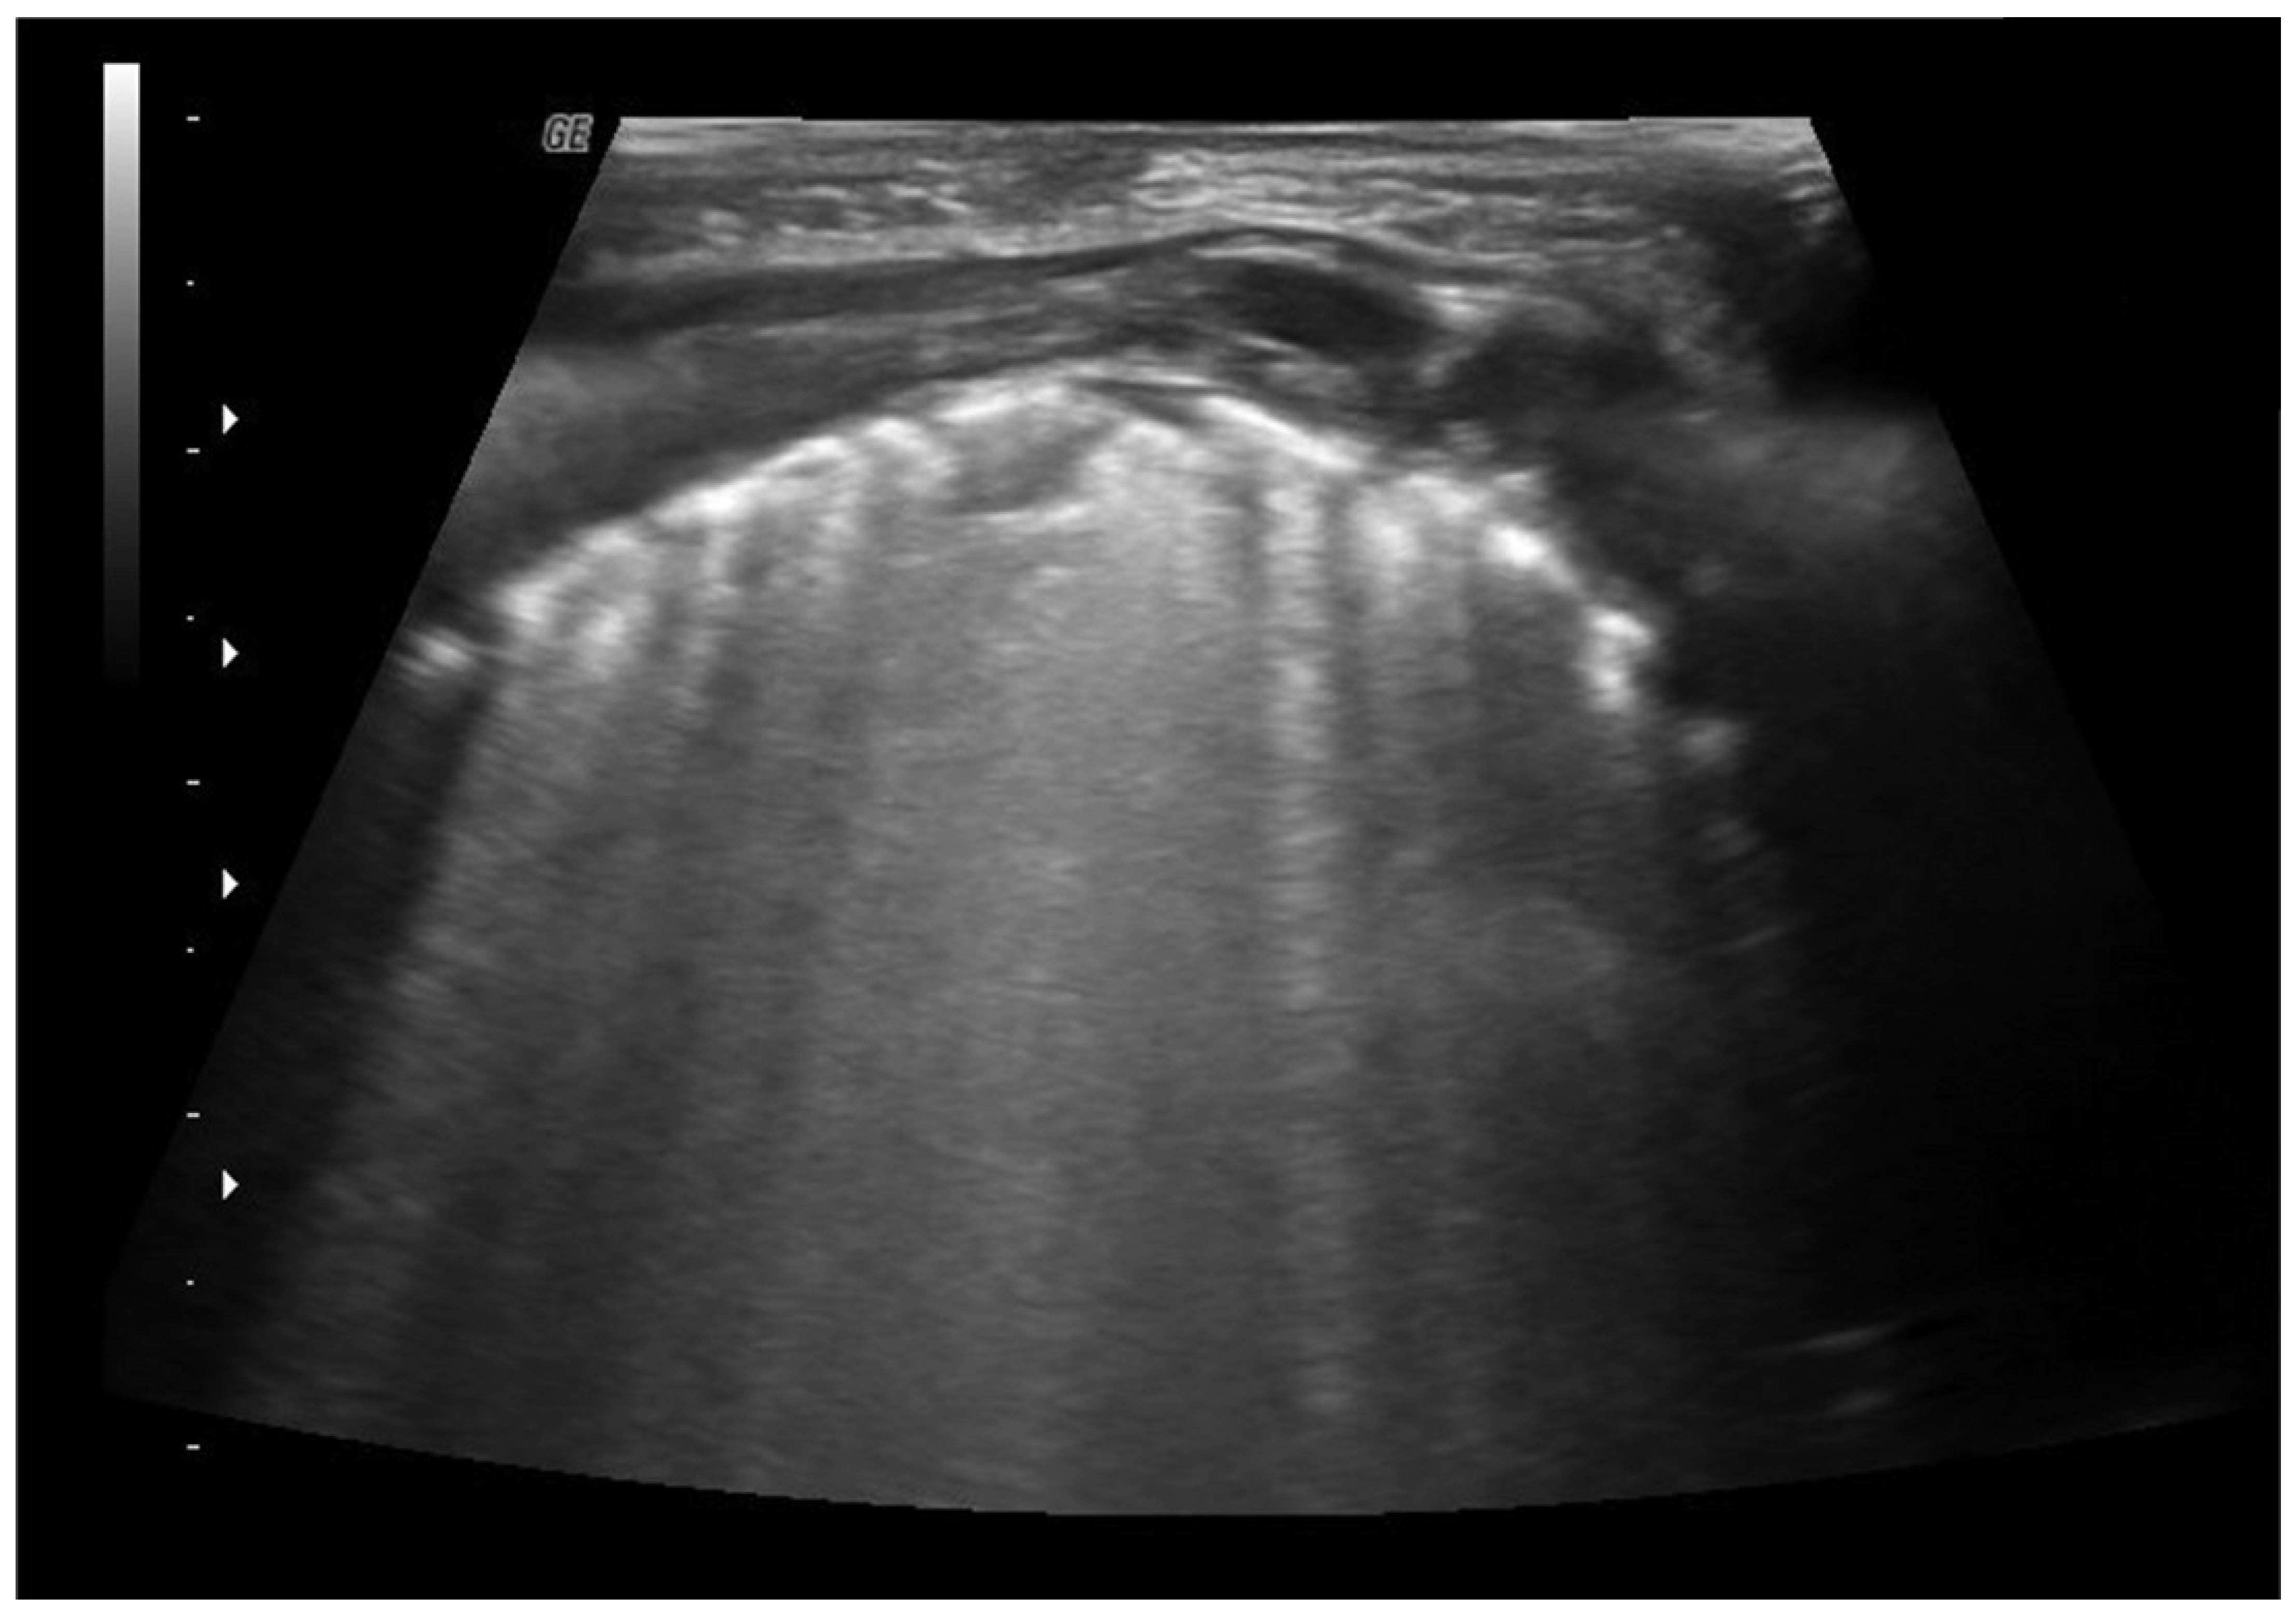

4.2. Pneumonia